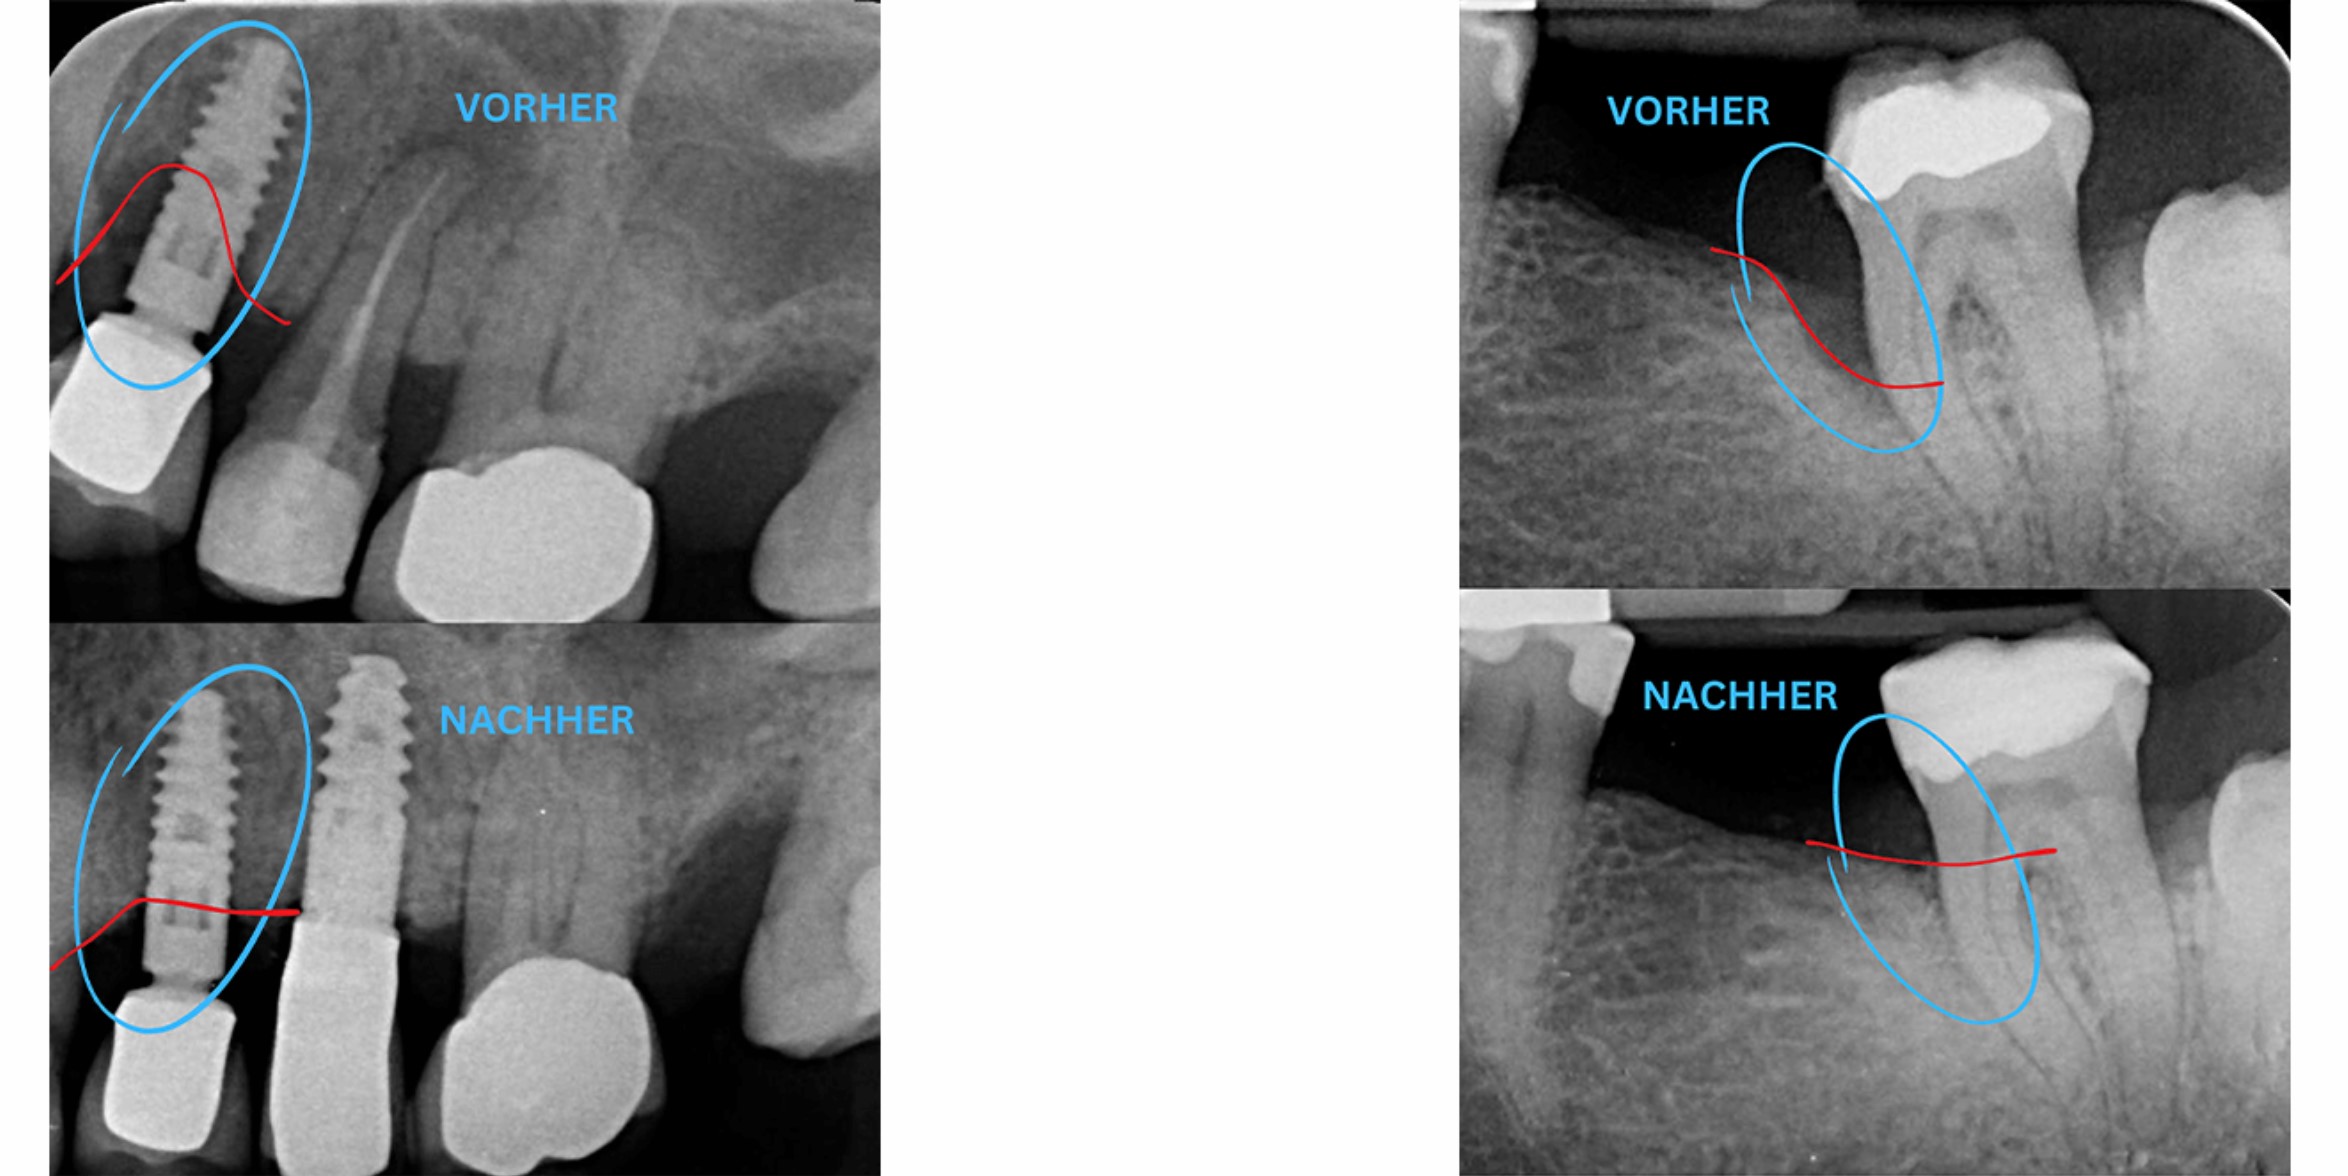

Периимплантит — это серьёзное заболевание, которое в результате воспалительной реакции может привести к разрушению костной ткани вокруг зубных имплантатов. Часто этот процесс протекает без боли и хронически, что означает, что пациенты могут долгое время не замечать проблему. Основной причиной периимплантита обычно является биоплёнка, образующаяся бактериями на поверхности имплантата под десной. Если это состояние не лечить, оно может привести к потере имплантата.

Наши специализированные методы удаления биоплёнки позволяют эффективно остановить воспалительный процесс вокруг имплантата. Во многих случаях нам даже удаётся восстановить уже утраченную костную ткань с помощью современных регенеративных методов. В более тяжёлых случаях мы также предлагаем удаление и повторную установку поражённого имплантата.

Интересно, что наш подход к лечению периимплантита может применяться и к естественным зубам, чтобы стимулировать регенерацию и восстановление костной ткани в данной области. Благодаря нашему опыту и профессионализму в ZAHN33 мы стремимся сохранять и улучшать здоровье полости рта наших пациентов в Берлине и за его пределами.